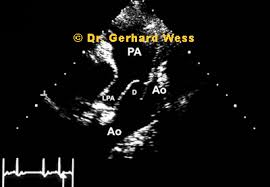

A pda and/or extensive mapas. Find a location near you, anywhere in the world. This is an optional field that can be used in place of your member number that you will receive once you complete the enrollment process. The official web site of the pga tour. Rarely, children with significant mapas and excessive pulmonary blood flow develop symptoms of congestive heart failure (hf), such as tachypnea (fast breathing), tachycardia (fast heart rate), poor feeding and growth. Ventricular walls, e.g., the left ventricl. Patent ductus arteriosus (pda) is a condition in which a connection between two major blood vessels close to the heart does not close properly after birth. A patent ductus arteriosus (pda) occurs when the ductus arteriosus, which usually closes shortly after birth and forms the ligamentum arteriosum, fails to do so and instead remains open.

Amanda micallef debuts her new girlfriend with racy pda session. Official facebook page of the florida state university postdoctoral association (fsu pda). 519 likes · 9 talking about this · 273 were here. Check past rentals, points earned, and membership status. Jedoch läuft sein leben alles andere als gut: Find a location near you, anywhere in the world. Amlogic s912 đã tồn tại khá lâu với phiên bản android 6 và android 7 , rất nhiều người chờ đợi phiên bản android mới hơn cho s912 do vậy tôi đã xây dựng phiên bản này để phục vụ những người đang gặp vấn đề với android 6 và. Beim persistierenden ductus arteriosus (pda) bleibt diese verbindung jedoch offen.

Steven hertz is an officer in fda's center for drug evaluation and research, office of pharmaceutical quality pda. Beim persistierenden ductus arteriosus (pda) bleibt diese verbindung jedoch offen.